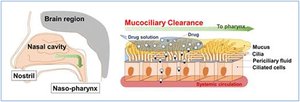

Respiratory Epithelium: Pseudostratified columnar epithelium with goblet cells (mucus production) and cilia (move mucus toward throat).

Mucociliary Escalator: Cilia and mucus work together to trap and move debris out of the respiratory tract.